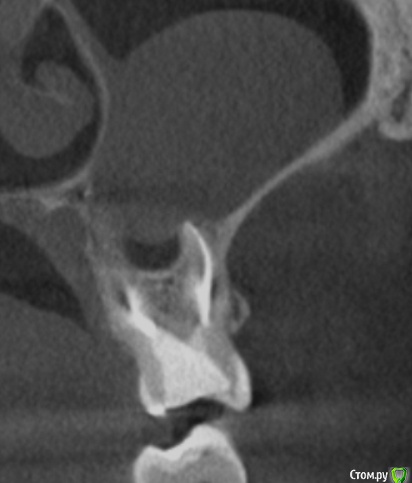

tineola Опубликовано 15 марта, 2017 Автор Поделиться Опубликовано 15 марта, 2017 Еще скриншоты. Другая проекция из КТ. Ссылка на комментарий